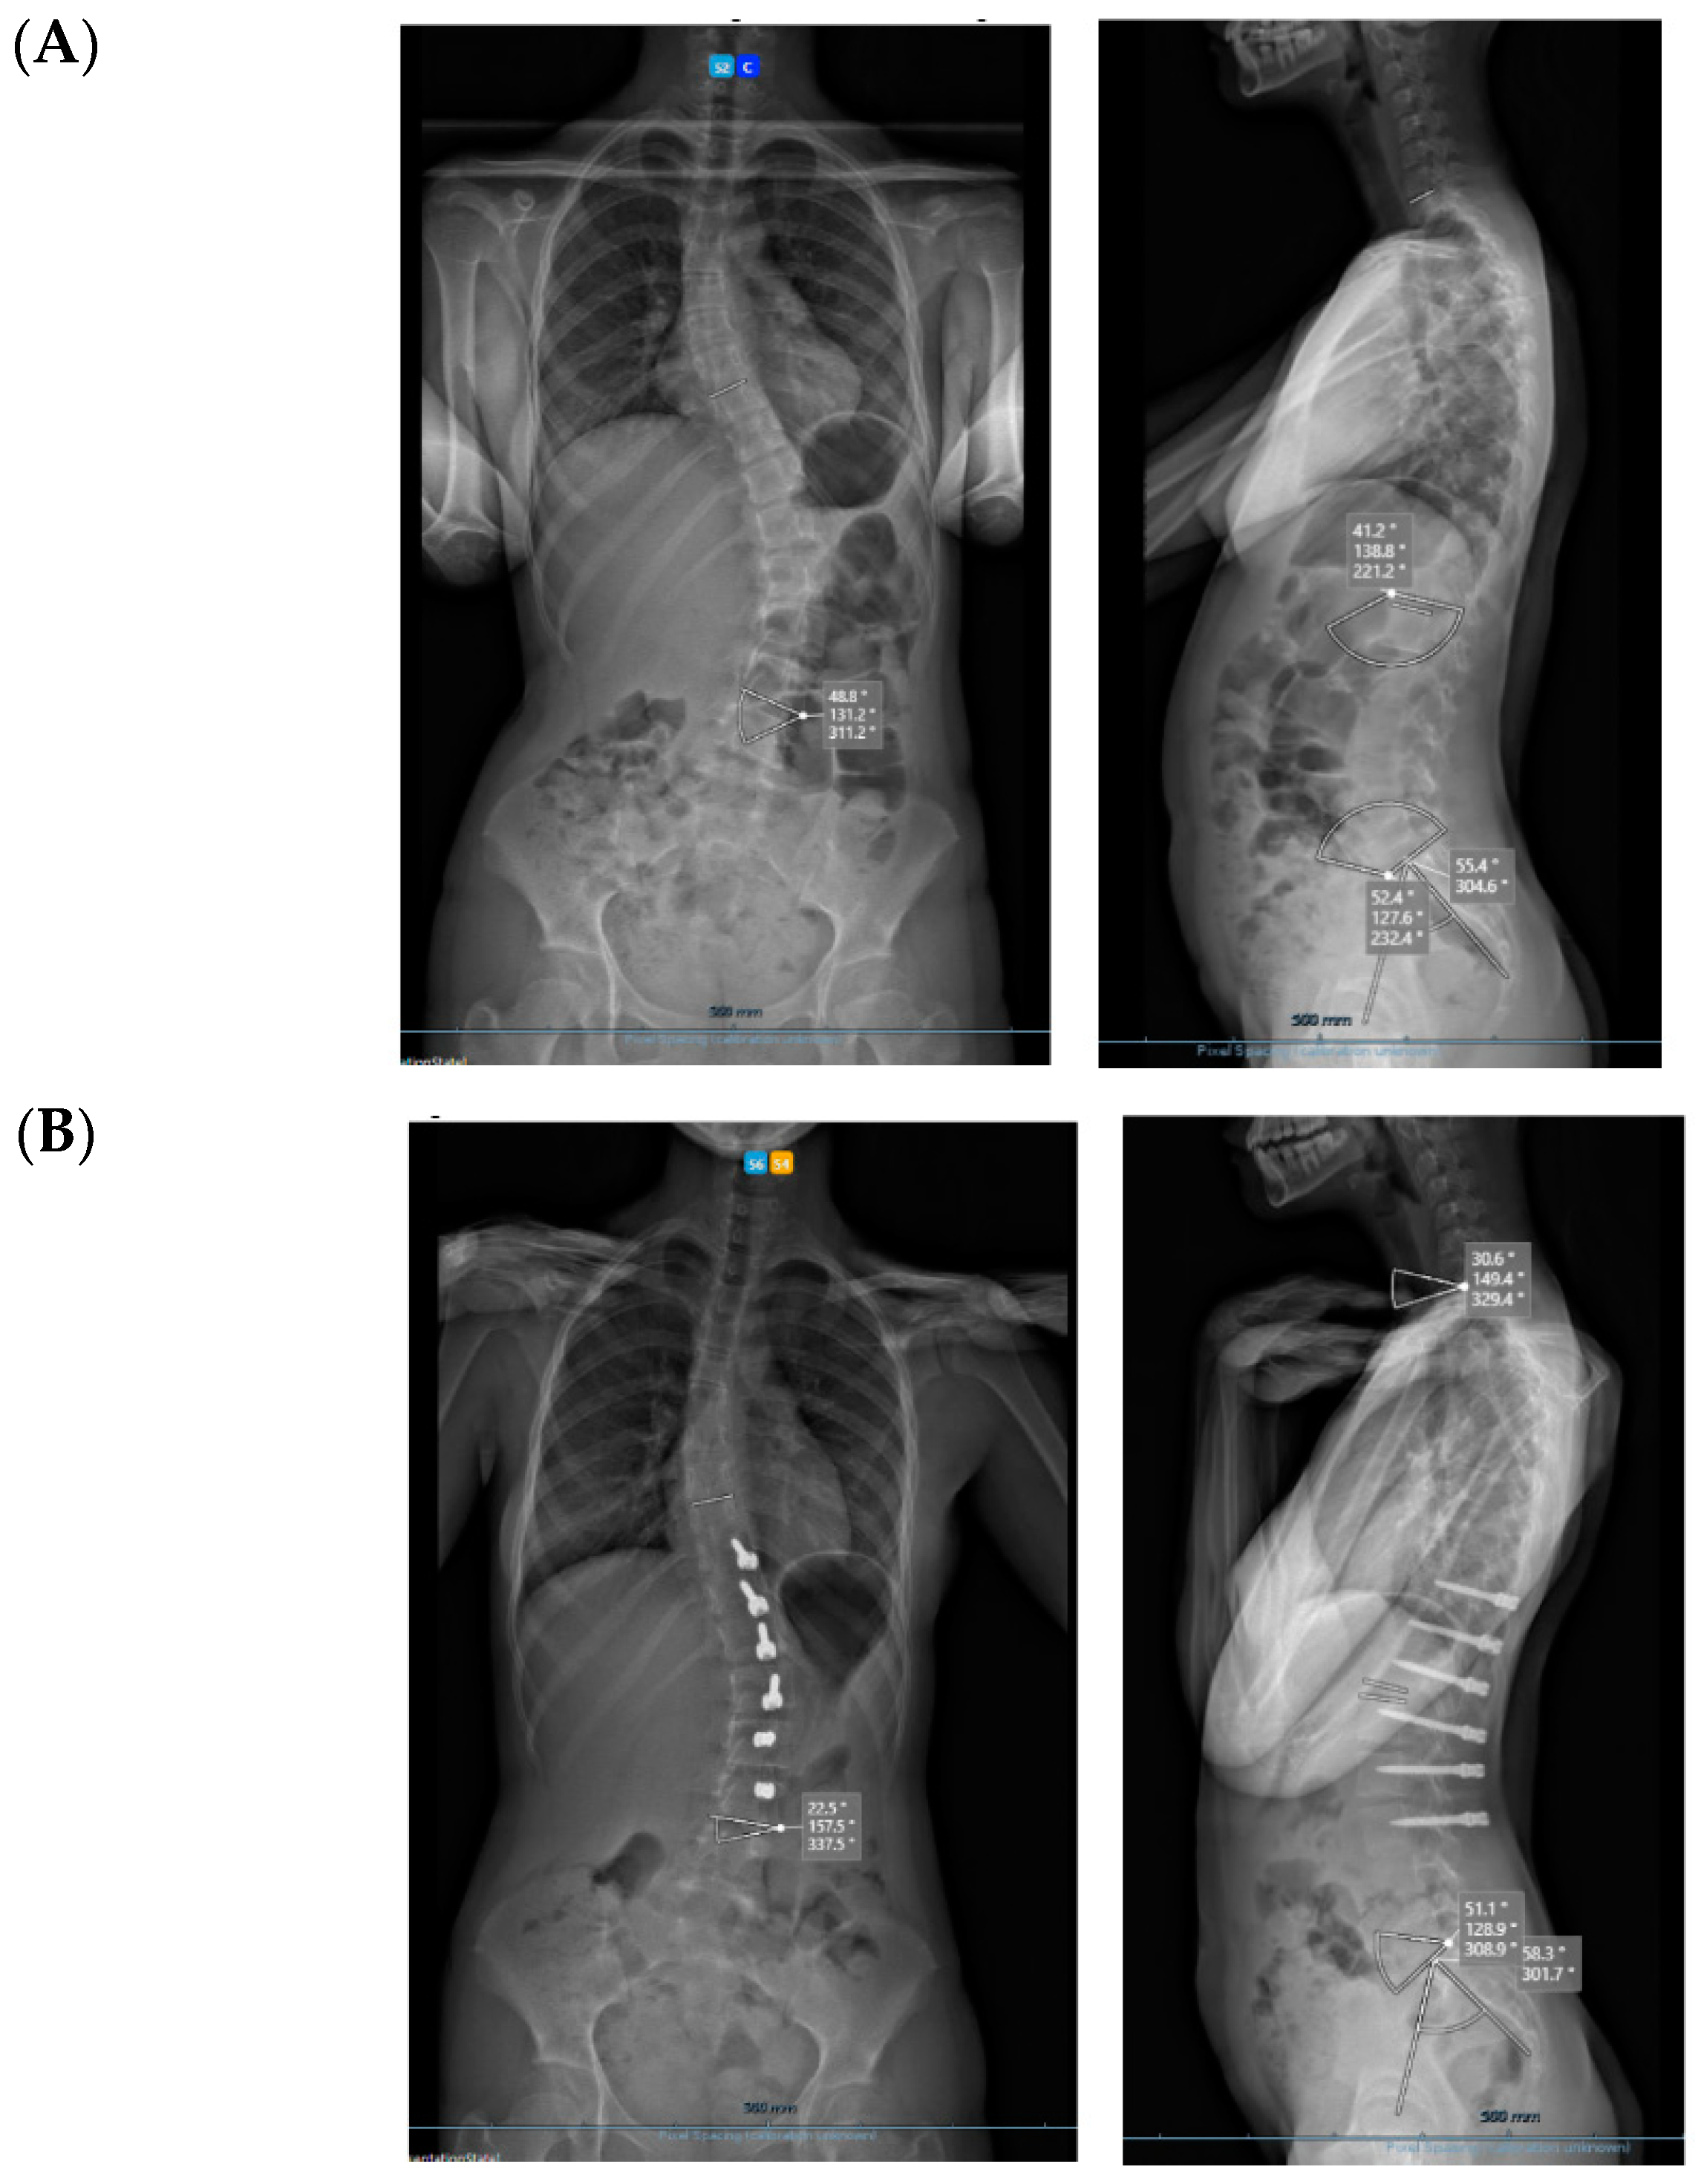

All three cases were thoracolumbar scoliosis (Lenke 5C) with an apex between T12 and L1 (Figure 3, Figure 4 and Figure 5).

Figure 3.

A 14-year-old adolescent. (A) Pre-op. (B) Immediate post-op. (C) One-year follow up.

Figure 4.

A 13-year-old adolescent. (A) Pre-op. (B) At 6-month follow up.

Figure 5.

A 14-year-old adolescent. (A) Pre-op. (B) At 6-month follow up.

As far as skeletal maturity is concerned, two cases were Sanders 3 (Risser 1 and 0) and one case was Sanders 5 (Risser 4).